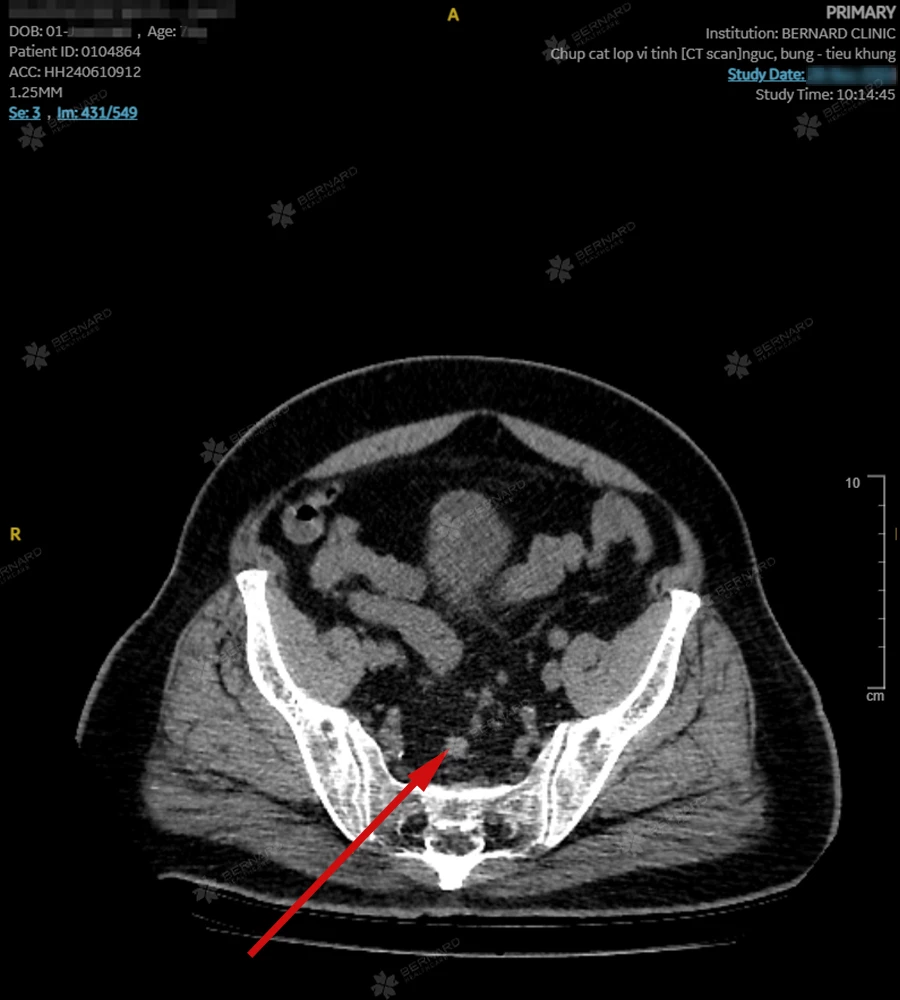

Ngoài ra, bệnh nhân còn thực hiện CT Scan vùng bụng - tiểu khung. Kết quả lớp cắt ghi nhận: Dày không đều thành trực tràng giữa-cao, dmax # 1.6cm, kéo dài một đoạn # 5cm, hình ảnh thể hiện dấu hiệu thâm nhiễm, kèm vài hạch nhỏ mô mỡ quanh trực tràng, dmax # 7mm.